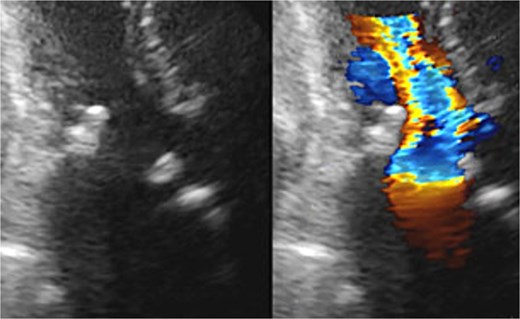

Seven pledgeted 2–0 Cardioxyl sutures were placed along the posterior mitral annulus, and a 27 mm Epic bioprosthesis (Abbott, St. Paul, MN, USA) was secured over two-thirds of the circumference. A folded 5 cm bovine pericardial patch (Edwards Lifesciences, Irvine, CA, USA) was attached to the remaining one-third using a 4–0 Prolene polypropylene running suture to create the left atrial roof and reconstruct the left ventricular outflow tract and noncoronary sinus of Valsalva. The aortic annulus was then reconstructed. The left and right coronary commissures were sutured from the left ventricular outflow tract toward the aortic side, while the noncoronary commissure was sutured from the external pericardial patch inward. A 23 mm Inspiris Resilia bioprosthesis (Edwards Lifesciences, Irvine, CA, USA) was implanted, and the remaining pericardium was used to close the aortotomy. The patient was extubated on postoperative Day 1 but required reintubation the same day because of pneumonia, which responded to antibiotics, allowing re-extubation on Day 7. Postoperative echocardiography revealed excellent hemodynamics: aortic valve effective orifice area (EOA) 1.76 cm2 with peak velocity 1.8 m/s and mean gradient 6 mmHg; mitral valve peak velocity 1.9 m/s and mean gradient 3 mmHg (Fig. 3). She was discharged on Day 21 and has remained free of heart failure.

Postoperative transthoracic echocardiography: normal function of both prosthetic valves without dysfunction.